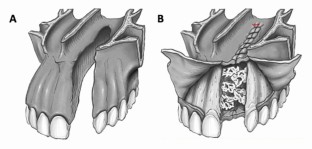

Primary cleft surgery refers to the planned surgical procedure(s) necessary to reconstruct an orofacial defect according to a specified protocol; in the context of a unilateral cleft lip and palate, this would include lip repair (with vomer flap closure of the hard palate), subsequent repair of the residual soft palate cleft and finally, the alveolar bone graft. This paper will provide an overview of the goals of primary surgical reconstruction, including the utility of pre-surgical orthopaedic techniques, including nasoalveolar moulding. The surgical methods of primary lip repair in both unilateral and bilateral clefts will be outlined and the concept of a primary rhinoplasty will be introduced. The principal techniques of cleft palate reconstruction will be delineated for a variety of cleft phenotypes. The final element of the primary reconstructive sequence is the alveolar bone graft using cancellous bone harvested from the iliac crest at approximately 8-10 years of age. The role of optimising oral hygiene prior to bone grafting cannot be over-emphasised and the utility of pre-surgical orthodontic arch expansion is also discussed. In the UK, bone graft outcomes are audited using the Kindelan score, which is evaluated from the six-month postoperative upper standard occlusal radiograph.

Outlines the reconstructive options for a patient with a unilateral cleft lip and/or palate, including contemporary cleft lip repair techniques, vomerine flap closure of the hard palate, and the importance of alveolar bone grafting.

Discusses the primary surgery options for a patient with a bilateral cleft lip and/or palate, and summarises the methods of bilateral cleft lip repair.